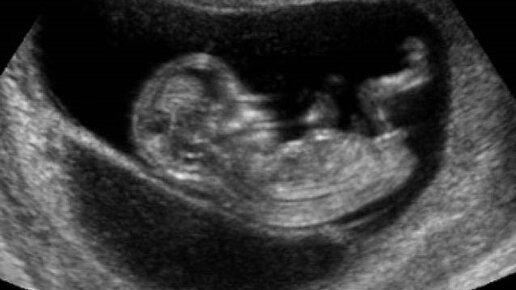

9 причин не отказываться от УЗИ во время беременности